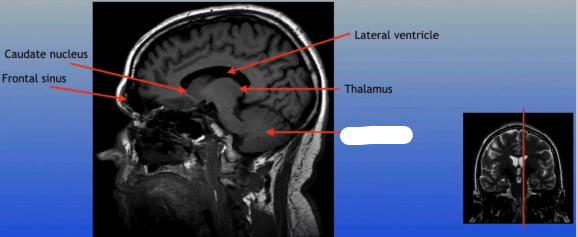

Caudate Nucleus

A C-shaped structure within the brain's basal ganglia, involved in various functions including motor control and learning.

Frontal Sinus

A paired cavity located within the frontal bone, above the eyes, that plays a role in sinus drainage and resonance of the voice.

Lateral Ventricle

A fluid-filled cavity located within each hemisphere of the brain, part of the ventricular system, that helps cushion the brain and circulate cerebrospinal fluid.

Thalamus

A large mass of gray matter located in the diencephalon, acting as a relay station for sensory information and playing a key role in regulating consciousness and sleep.